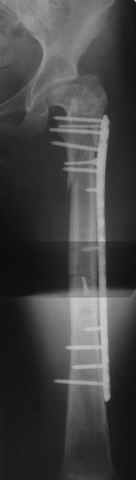

Уважаемые коллеги, приношу извенения за молчание. Готовили материал и боялись писать раньше времени. Все хотели убедиться в том, что после операции все будет спокойно. Спасибо за отклики и советы. К сожалению, гамма-гвоздя, штифтов с возможностью установки более 2-х блокирующих винтов у нас нет. Зато нашли достаточно длинную пластину с угловой стабильностью. После проведения предоперационной подготовки и планирования выполнили остеосинтез. В условиях рентгеноперационной, после репозиции дистрактором из одного разреза 5см в проксимальном отделе подкожно установили пластину. Пришлось выполнить дополнительный разрез до5см в проекции перелома диафиза в средней трети, из которого удалось репонировать перелом и выполнить фиксацию стягивающим винтом. Затем все завершилось наложением пластины с угловой стабильностью. Пластина оказалась достаточно длинной, что позволило перекрыть все переломы с фиксацией каждого отломка минимум 5-ю винтами. Синтез достаточно стабилен. Пациентка активизирована на 3-и сутки(снимки прилагаются). В настоящий момент пациентка выписана на амбулаторное лечение. Еще раз, огромное спасибо всем за помощь в выборе тактики и просто совете. С уважением Украинский Е.

Получилось очень симпатично, мои поздравления. А можно фото конечности без наклеек посмотреть?

И межфрагментарный винт на диафизе - так ли он нужен при выбранном варианте остеосинтеза с относительной стабильностью?

Хотя все-таки закрыто антгерадно заштифтовать тут было вполне можно, и при использовании отечетственного имплантата лечение обошлось бы на порядок дешевле. Опасения коллеги Кульджанова насчет кровоснабжения головки бедра и предстоящих операции в этой области кажуься несколько

преувеличенными - и стержень можно через вертел ввести, да и расстройства кровоснабжения головки, если они случатся после штифтования, не будут длиться вечно.

Но в люом случае, что сделано - то сделано, и сделанное выглядит вполне обнадеживающе, так что еще раз поздравляю коллег с успешным выходом из непростой ситуации.